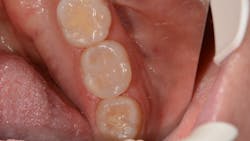

The failing composite restoration was removed along with the recurrent decay. A new restoration was placed using VisCalor bulk (figure 2). The flowability of theClinical case no. 2